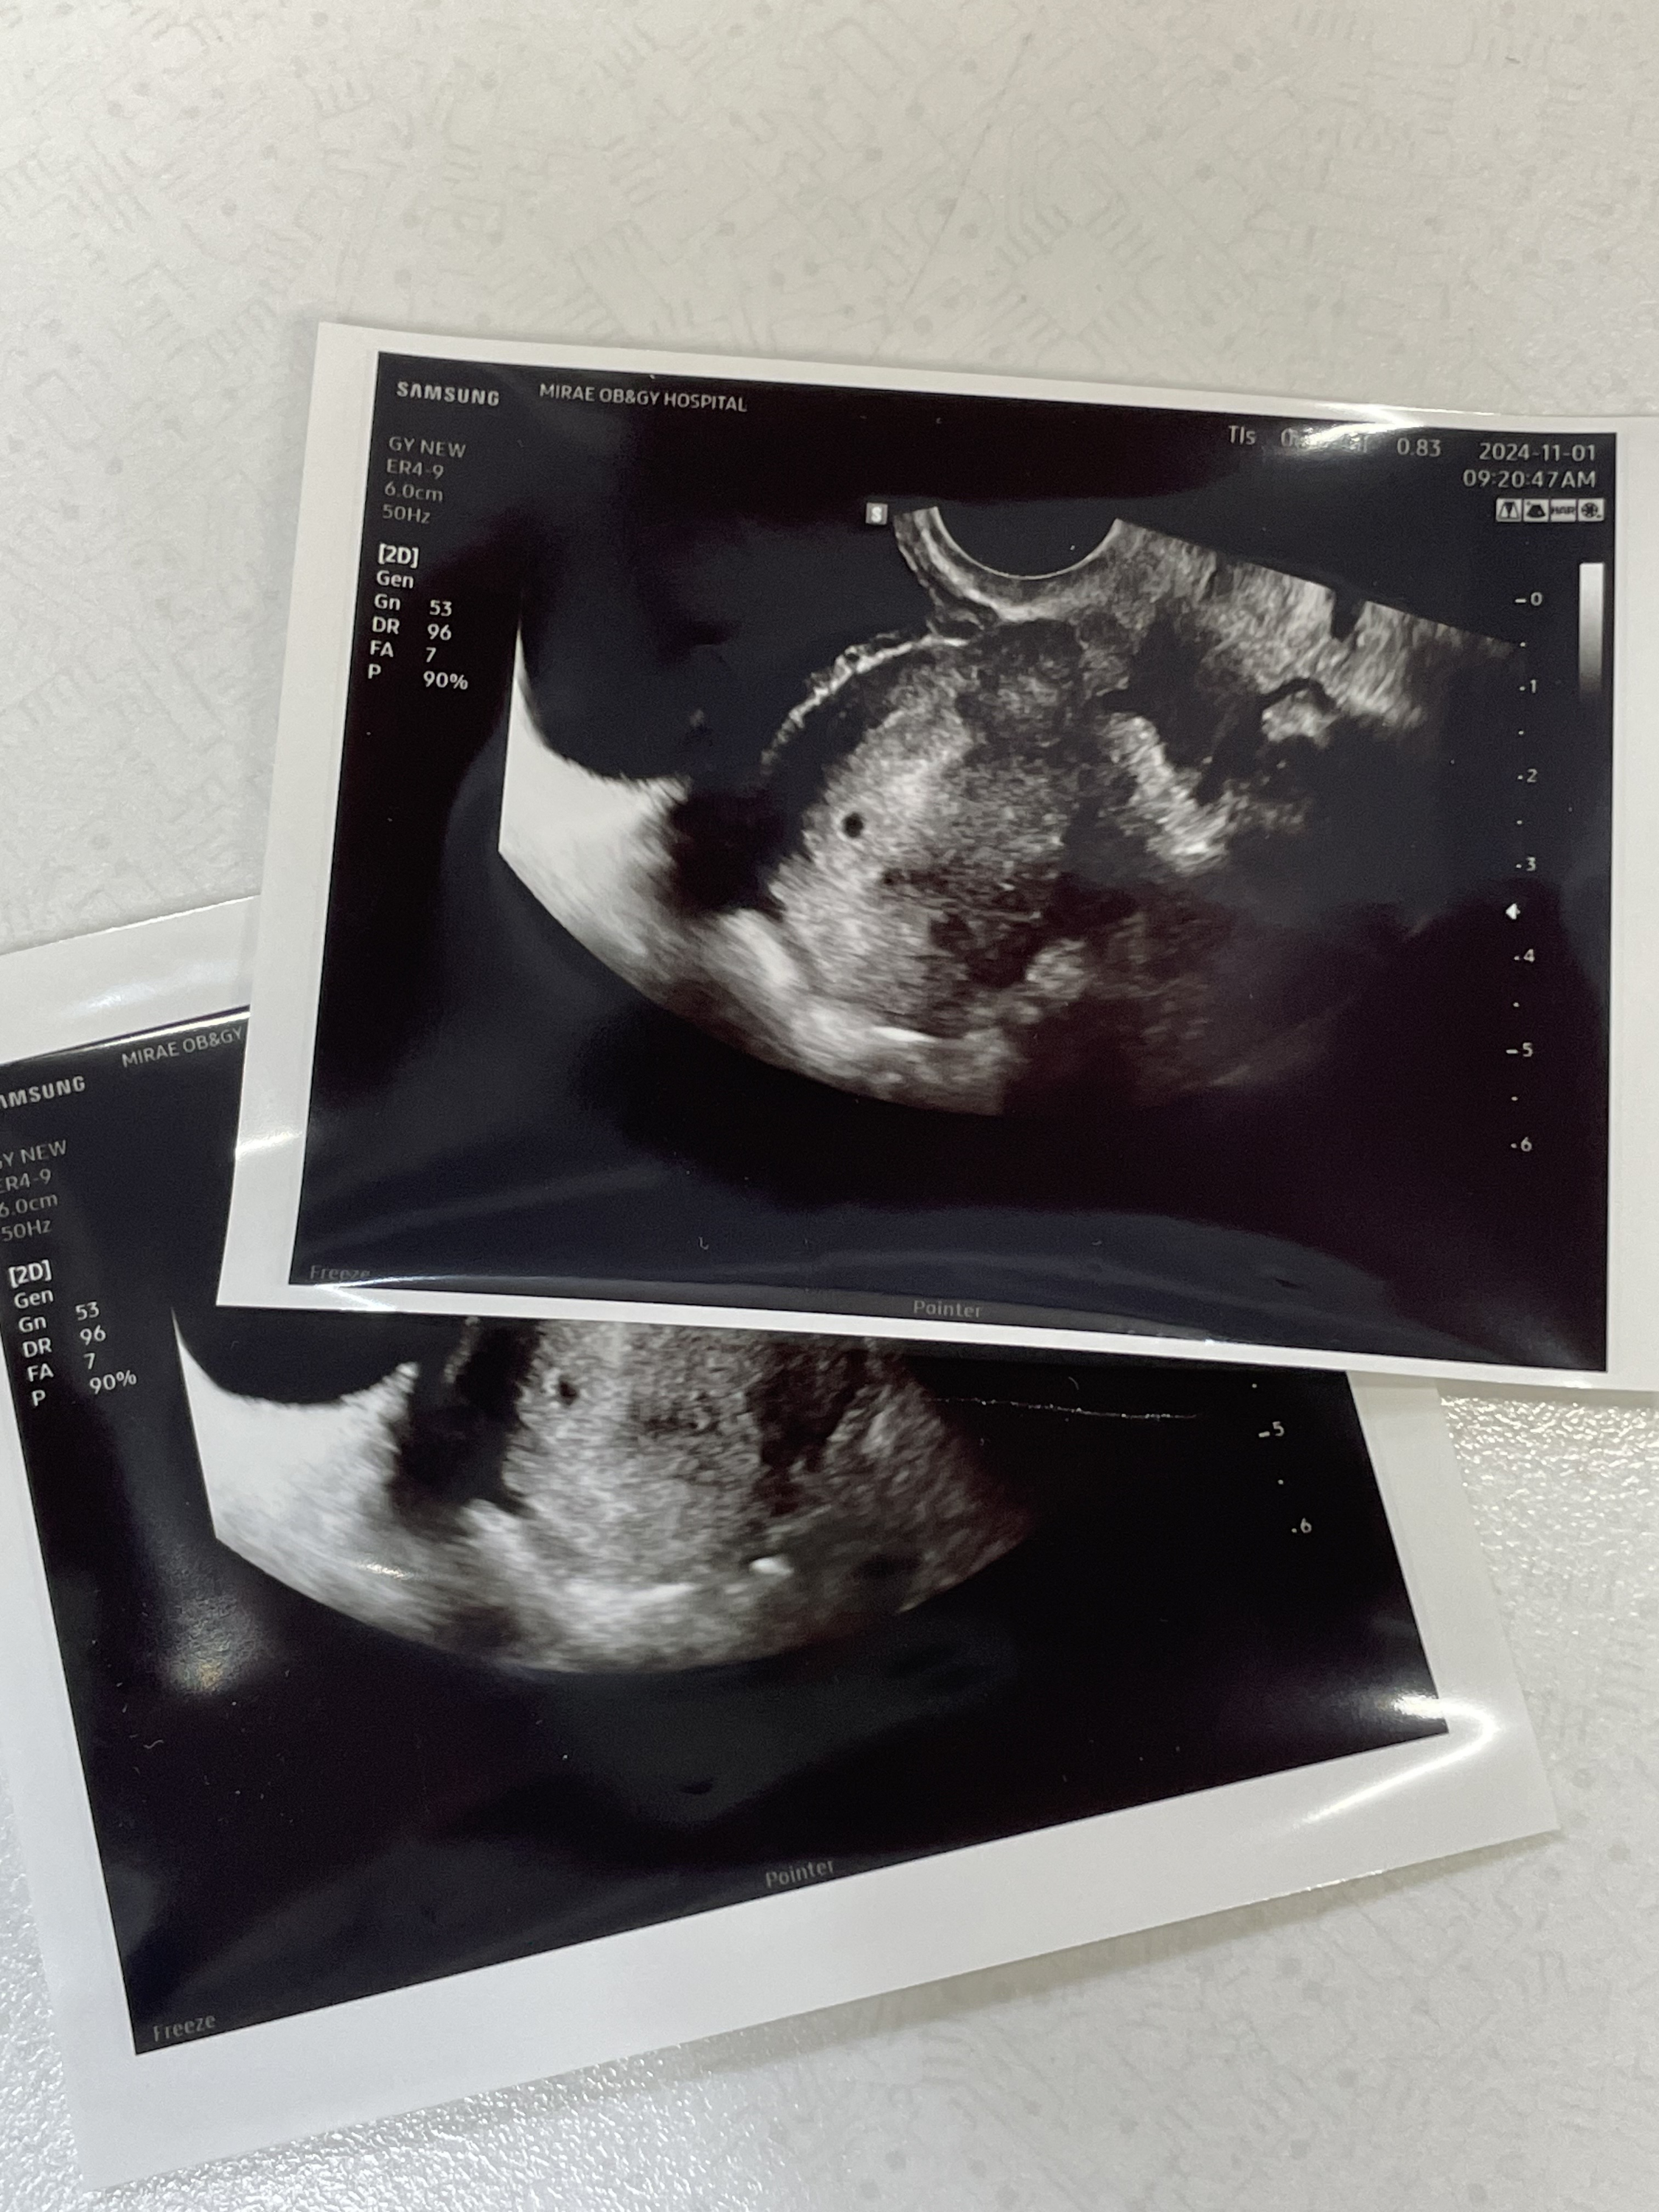

친절하고 상냥하신 원장샘께서 초음파를 보자고 하셔서 초음파를 봤더니

요기 콩알만한 복덩이가 있었따 이야.. 정말 쪼끄맣구나.. 귀여워 벌써

사이즈를 재보시더니 딱 5주 1일차 사이즈에 맞게 아주 잘 자라고 있다고 하셨다🤍

선근증에 대해서 여쭤보니 자궁 뒷편이 뚱뚱한게 선근증이 있는건 맞지만

사이즈가 그렇게 크지 않다셔서 그냥 출산하시면 된다고 하셨다.